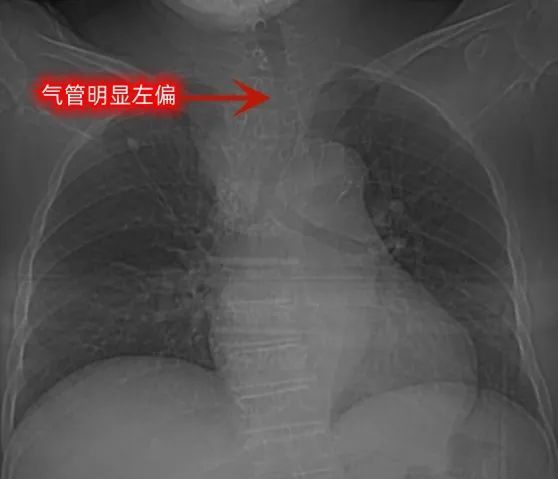

近日,1位72岁高龄女性患者因体检发现双侧甲状腺结节来院就诊,由于自觉肿块有进行性增大,门诊查B超提示双侧甲状腺结节性病灶:TI-RADS 3类;双侧甲状旁腺区未见明显异常;双侧颈部未见明显异常肿大淋巴结。入院后患者行甲状腺增强CT示胸骨后巨大甲状腺肿,呈葫芦状,向纵隔延伸至气管隆突下方,考虑行传统颈部入路甲状腺切除手术难以做到根治,可能需胸腔镜辅助或胸骨正中劈开下行手术才能完整切除肿瘤。进一步行胸部增强MR示:上纵隔肿瘤性病变,起源于右侧甲状腺可能,倾向胸骨后甲状腺肿可能;双侧甲状腺结节,良性可能,考虑结节性甲状腺肿。患者完善检查后无明显手术禁忌症,但是患者胸部CT及胸部MR均提示患者部分气管向左偏移,且局部管腔狭窄,麻醉科术前探视及评估后认为,由于气管中段受压变形及移位,气管插管过程中可能会出现气管插管困难、失败、气管损伤穿孔,甚至是气管痉挛导致患者窒息和意外死亡,麻醉风险极高。

根据患者病史及影像学特点,诊断上考虑为胸骨后巨大甲状腺可能性大,该病一般为良性疾病,患者平素呼吸系统症状不明显,CT及MRI虽然提示气管受压,但尚未造成严重狭窄及气管梗阻,应争取手术解除气管外压迫,故有手术指征,但是该肿瘤位置较低,并且肿大的甲状腺造成一定程度的气管受压移位,围术期手术风险较大,应该综合考虑手术风险,充分与家属沟通病情后进一步治疗。